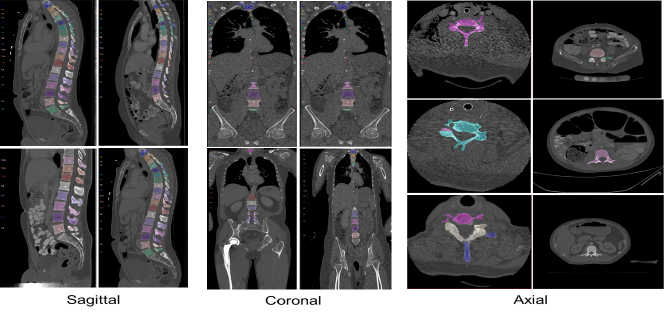

The xVertSeg dataset was released in xVertSeg challenge of MICCAI 2016 [26]. The dataset provides vertebral deformities, spine curvatures, and varying fields-of-views (FOVs). Fifteen train CT volumes with ground truth segmentation of the lumbar vertebrae (into five classes, L1-L5) and ten test CT volumes are included. The dataset consists of the ground truth for both localization and segmentations. In our study, our focus is on the segmentation part. Figure 2 depicts some samples of xVertSeg dataset from different views.

Moreover, the segmentation results generated by DoubleU-Net and DoubleU-Net++ are provided in Figure 7 and Figure 8 for VerSe2020 and xVertSeg datasets, respectively. Each row depicts an image on sagittal view. The first and second columns show the segmented image, described in Section 3.3.2 (Figure 3), and the third and fourth columns illustrate the final output of DoubleU-Net and DoubleU-Net++, respectively. Compared with DoubleU-Net the final outputs of DoubleU-Net++are more close to the ground truth which is shown in the last column.